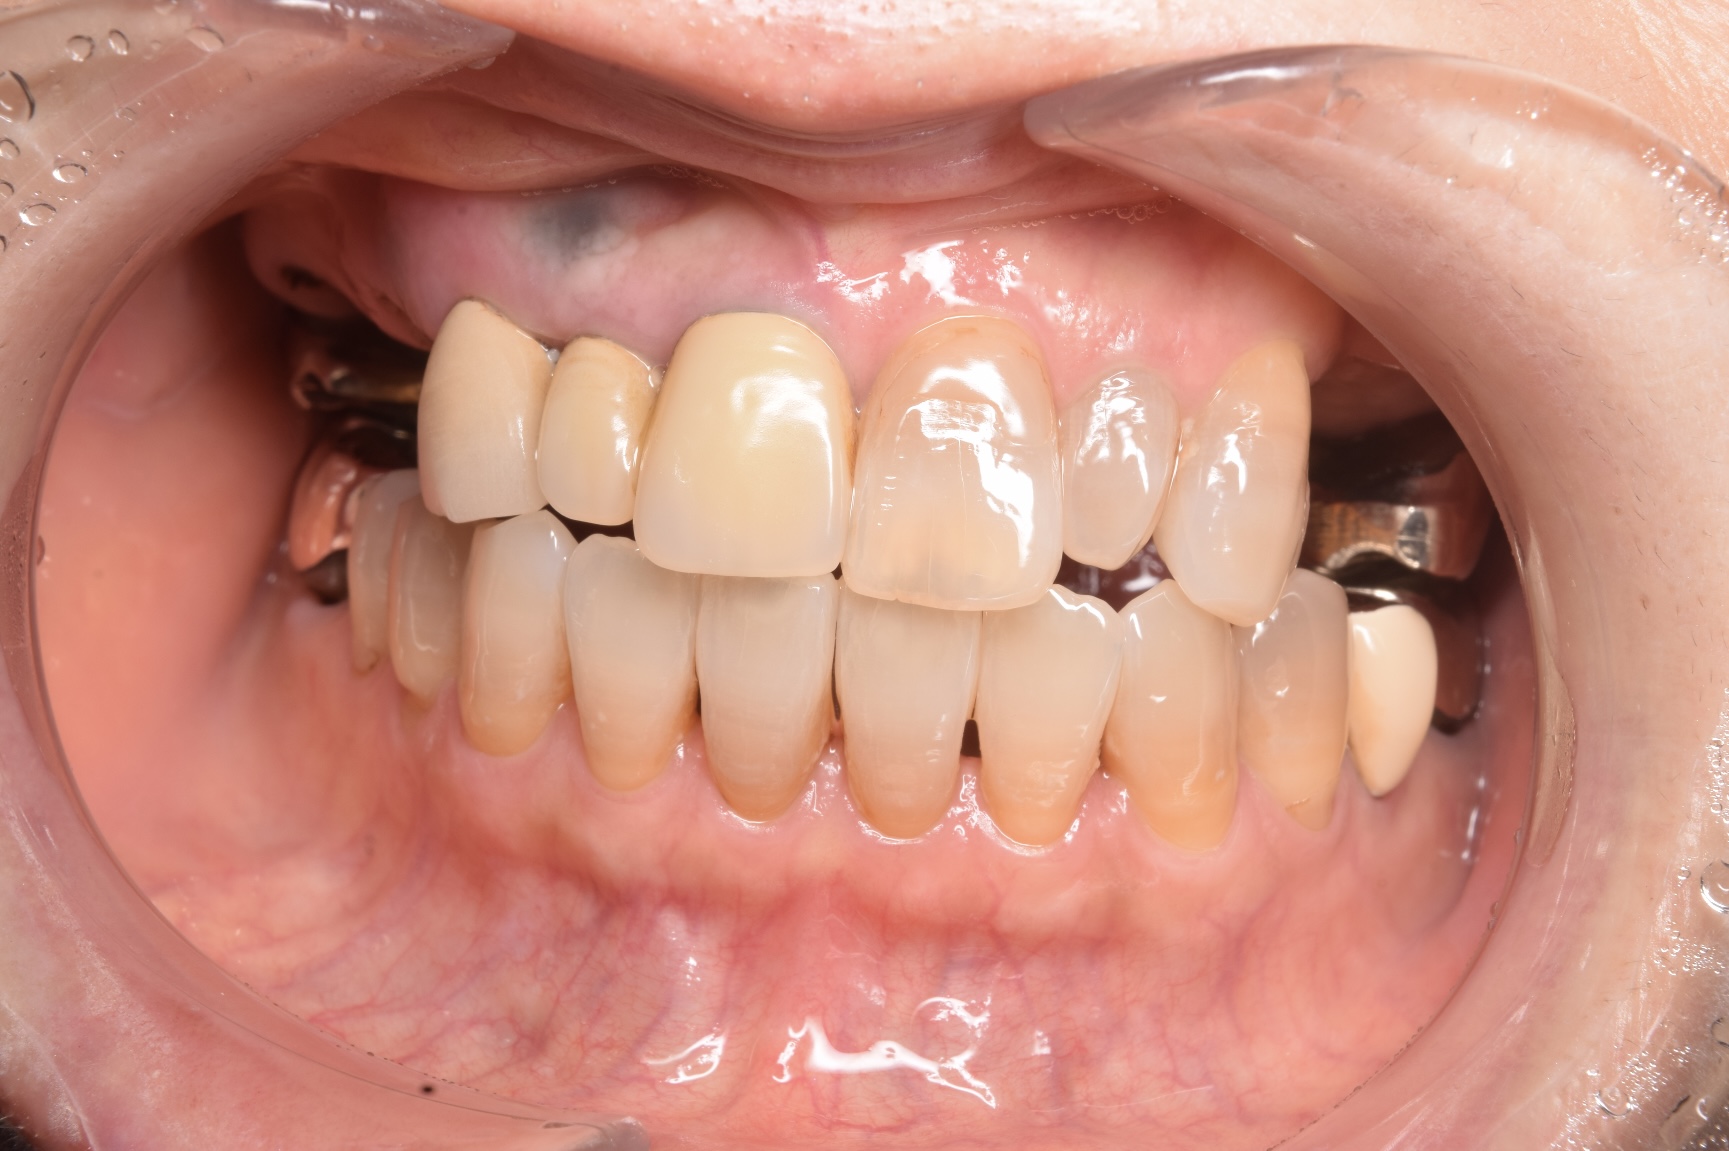

CASE

ご来院の動機